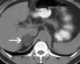

Adrenal adenoma

Adrenocortical adenoma is commonly described as a benign neoplasm emerging from the cells that comprise the adrenal cortex. Like most adenomas, the adrenocortical adenoma is considered a benign tumor since the majority of them are non-functioning and asymptomatic. [Source: Wikipedia ]